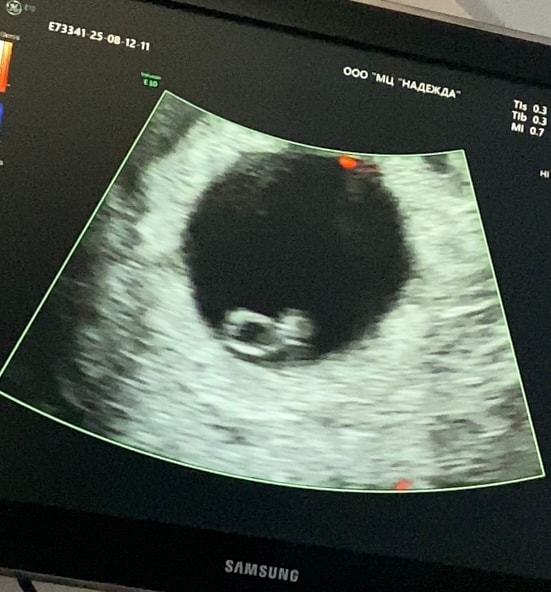

привет, девочки👋🏻🌸 нашли эмбрион и услышала сердечко❤️🥹 и такие данные:

СВД ПЯ 17 мм.

КТР эмбриона 3,3 мм

желточный мешочек 3,6 мм

ЧСС 118 уд/мин.

хорион локализация задняя стенка 5 мм. желтое тело в правом яичнике диаметром 13 мм.

врач сказала, что все соответствует сроку 6 недель и все хорошо🙌🏻 а я умная такая🫠😂 вычитала в гугле что ктр немн